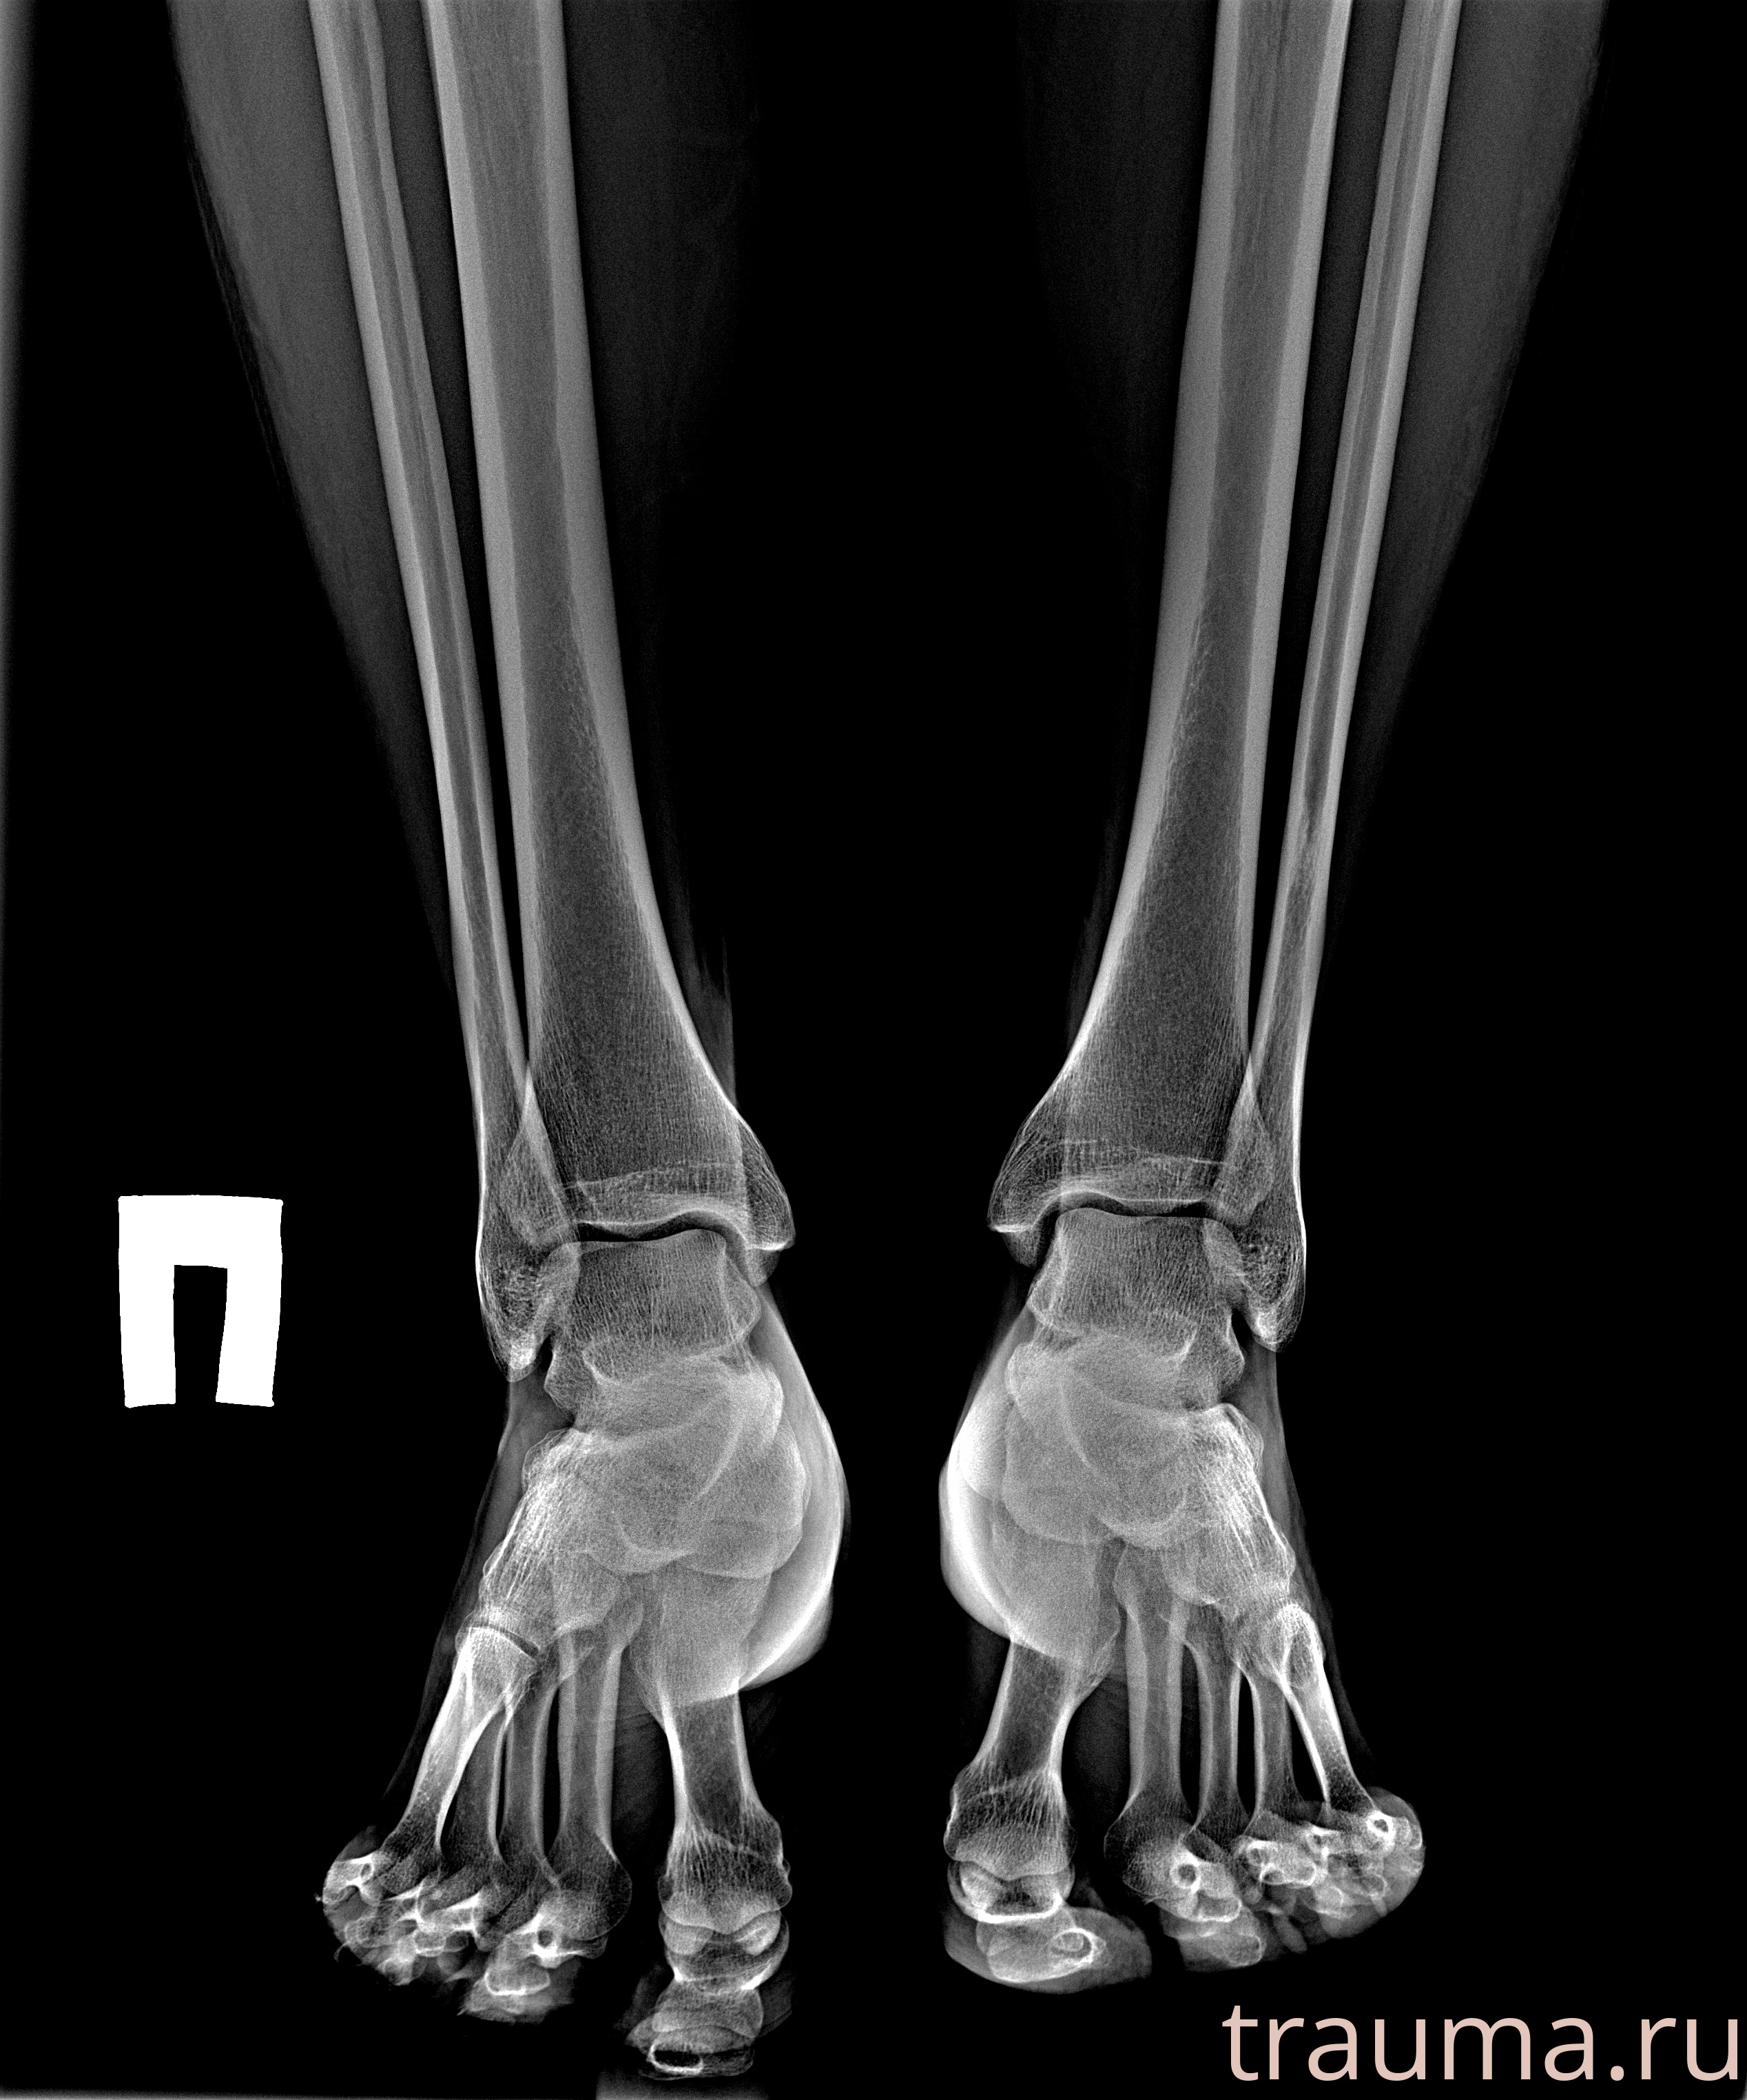

Рентгенограммы

Рентген на дому: по вашему адресу приезжает врач-рентгенолог, травматолог-ортопед с мобильным рентгеновским аппаратом, проводит диагностику травмы или заболевания, делает необходимые рентгенограммы, дает рекомендации по дальнейшему лечению. Получить качественные снимки в домашних условиях возможно благодаря уникальной методике, разработанной МосРентген Центром для института  Склифосовского